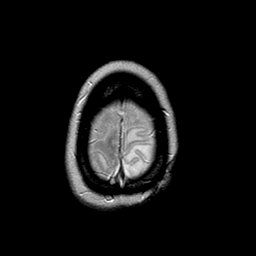

MR Study #2 -- Slice #47